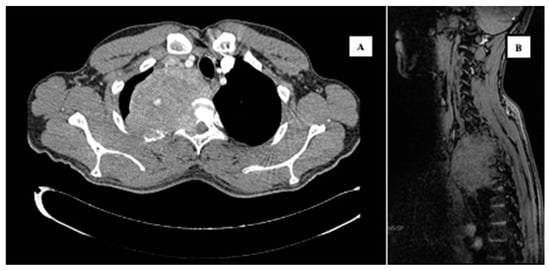

2. Case Report